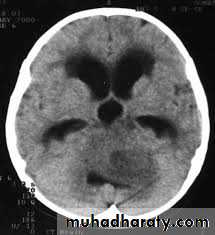

Posterior fosse tumor

Medullo blastomaAge incidence between 5-15 Y represent about 35-40 %of PFT

Arise from the midline mainly within or from the roof of the 4 TH ventricle fill the fourth ventricle & seeding via the csf so can seen in the distal part of the spinal canal .

CT finding as well circumscribed lesion heterogeneous in density ,have solid & cystic part , with also scattered calcification little surrounded edema , the solid part is enhance

90 % present with obstructive hydrocephalous at the level of the 4Th V. with dilatation of the lateral V. ( body , frontal , temporal & third ventricle )